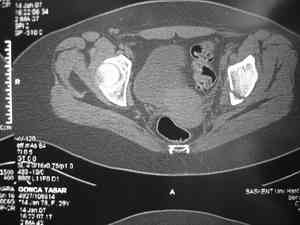

Dear group,30 years age female MVA front seat, head trauma + post column left acetabular fracture, 2.5 weeks skeletal traction. She is now conscious but still confused without any surgical treatment for brain edema.

Latest X rays and CAT is attached.Fracture within first 1.5 cm from the weight bearing dome, although AP and Obtrator oblique good, iliac oblique view reveals some displacement.I'm not sure that nonsurgical treatment will be OKHüseyin DemirorsBaskent UniversityDept of Orthopedics and TravmatologyAnkara TURKEY

CT scan taken 5 days ago and radiographs taken today

I may get beat up for this, but I see very little displacement that concerns me on the CT. The radiograph is more concerning. I suspect it could look better, and the gap made smaller on CT. Not sure if it will affect outcome. I might give it a shot and try to see what could be done.